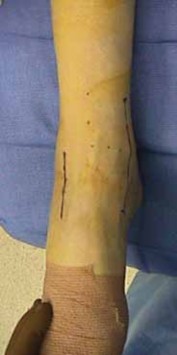

Medial and Anterolateral Approach

1. Anatomic reduction of displaced head, neck, and body fractures requires visualization of both medial and lateral surfaces of the talus. A medial and anterolateral (two-incision) approach effectively prevents a malreduction of the articular surfaces and neck. 2. A surgeon’s initial impression of the dual-incision approach to talus fractures may be perceived to disregard the biology of the bone and its limited extraosseous blood supply. With attention to detail, neither the plantar nor the direct dorsal blood supply to the talus is violated. 3. Landmarks for the medial incision are the dorsomedial tip of the medial malleolus extended, in line with the axis of the foot to the tarsal navicular ( FIG 4A). 1. This incision is 5 mm dorsal to the axis of the posterior tibial tendon. 2. Its extension continues just distal to the navicular tuberosity, allowing exposure of the medial surface of the talar head, neck, and distal body. 3. The approach may be lengthened in both directions to improve visibility. 4. The anterolateral incision is parallel and 5 to 6 cm lateral to the medial approach ( FIG 4B).

--- B ### FIG 3 • A. Supine position for medial and anterolateral approaches. B. Supine position for direct lateral A C approach. C. Prone position for posterior approach.

--- Anterior tibial tendon sheath Medial talar neck fracture

--- Lateral head of talus Extensor digitorum tendon Posterior tibial 1. tendon sheath Lateral talar 2. neck fracture Sinus tarsi ### FIG 4 • A. Medial approach. B. Anterolateral approach.